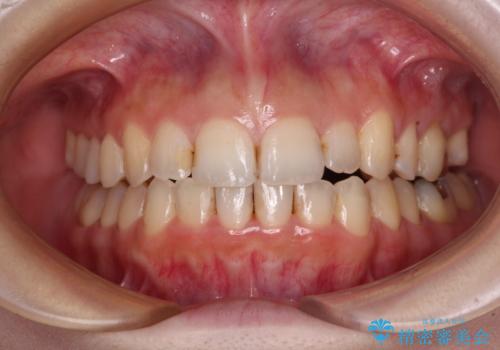

抜歯矯正で閉じにくかった口を閉じやすく改善

補助装置を使ったインビザラインによる抜歯矯正